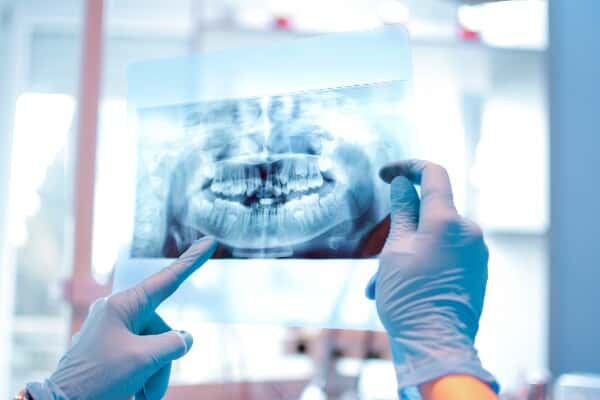

Dental X-rays are tools used in general dentistry to help patients and providers get a better understanding of the health of the teeth and mouth. These are considered both diagnostic and preventative resources, and patients experience little discomfort for the procedure. There are a variety of dental X-ray options, as each has a different purpose and can present different information to a dental provider.

Dental X-rays are tools used in general dentistry to help patients and providers get a better understanding of the health of the teeth and mouth. These are considered both diagnostic and preventative resources, and patients experience little discomfort for the procedure. There are a variety of dental X-ray options, as each has a different purpose and can present different information to a dental provider.

Images of the teeth provide a better picture of a patient’s oral health. Low levels of radiation from the X-rays take a picture of what is happening inside the teeth or gums. These images reveal impacted teeth, cavities, and tooth decay. Dental X-rays can show several things:

Panoramic X-rays

This imaging is generally used every three to five years for an overall mouth evaluation. It could also be recommended prior to an oral or orthodontic procedure.